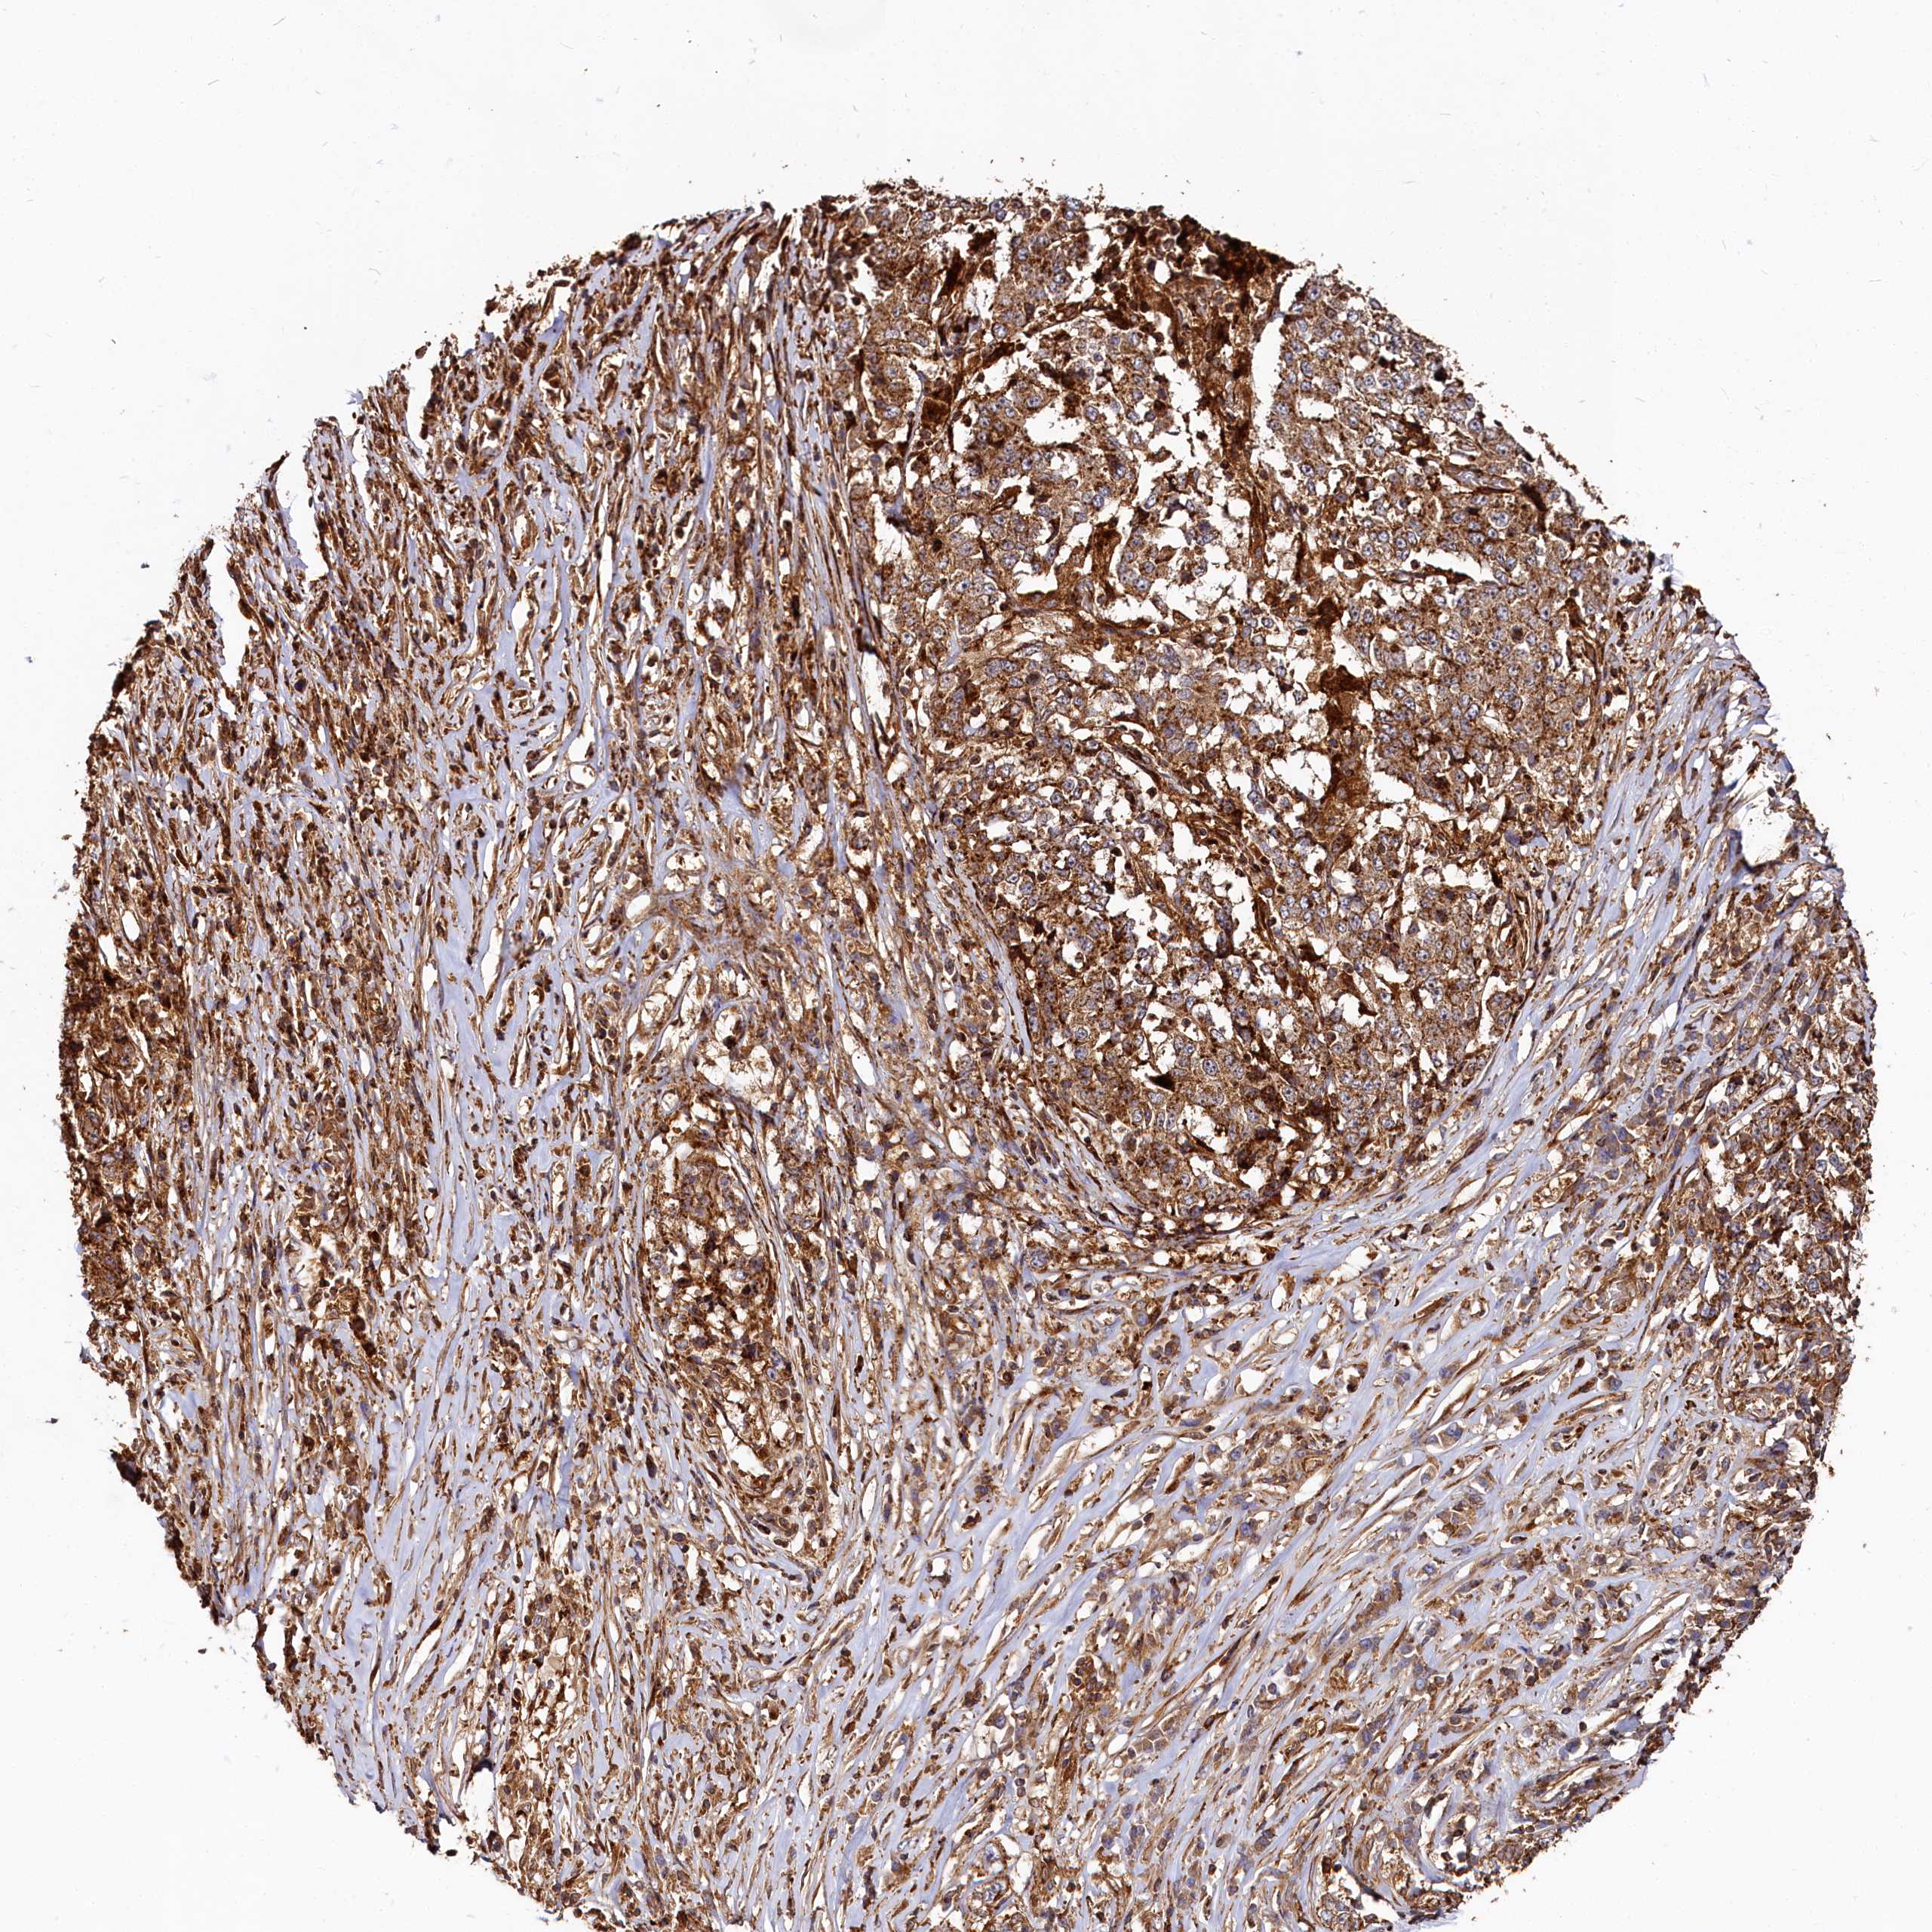

STOMACH CANCER - Protein expressioni

A mouse-over function shows sample information and annotation data. Click on an image to view it in a full screen mode. Samples can be filtered based on level of antibody staining by selecting one or several of the following categories: high, medium, low and not detected. The assay and annotation is described here.

Antibody stainingi

Antibody staining in the annotated cell types in the current human tissue is reported as not detected, low, medium, or high, based on conventional immunohistochemistry profiling in selected tissues. This score is based on the combination of the staining intensity and fraction of stained cells.

Each image is clickable and will lead to virtual microscopy that enables deeper exploration of all samples and also displays staining intensity scores, fraction scores and subcellular localization as well as patient and tissue information for each sample.

Antibody HPA039357

Staining

High

Medium

Low

Not detected

Intensity

Strong

Moderate

Weak

Negative

Quantity

>75%

75%-25%

<25%

None

Location

Nuclear

Cytoplasmic/membranous

Cytoplasmic/membranous,nuclear

Adenocarcinoma, NOS

Adenocarcinoma, High grade